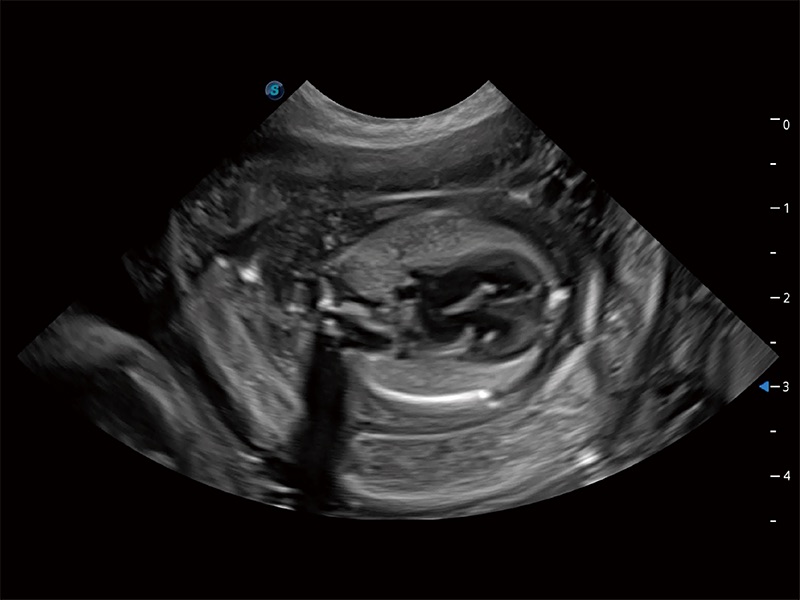

ProPet 80 全新的动物超声智能软件和丰富的探头群,为动物医生提供了高清晰度和精细分辨率的图像,无论在宠物、马科、畜牧还是实验室动物等应用中都可以轻松应对,为您的日常工作带来满意的体验。